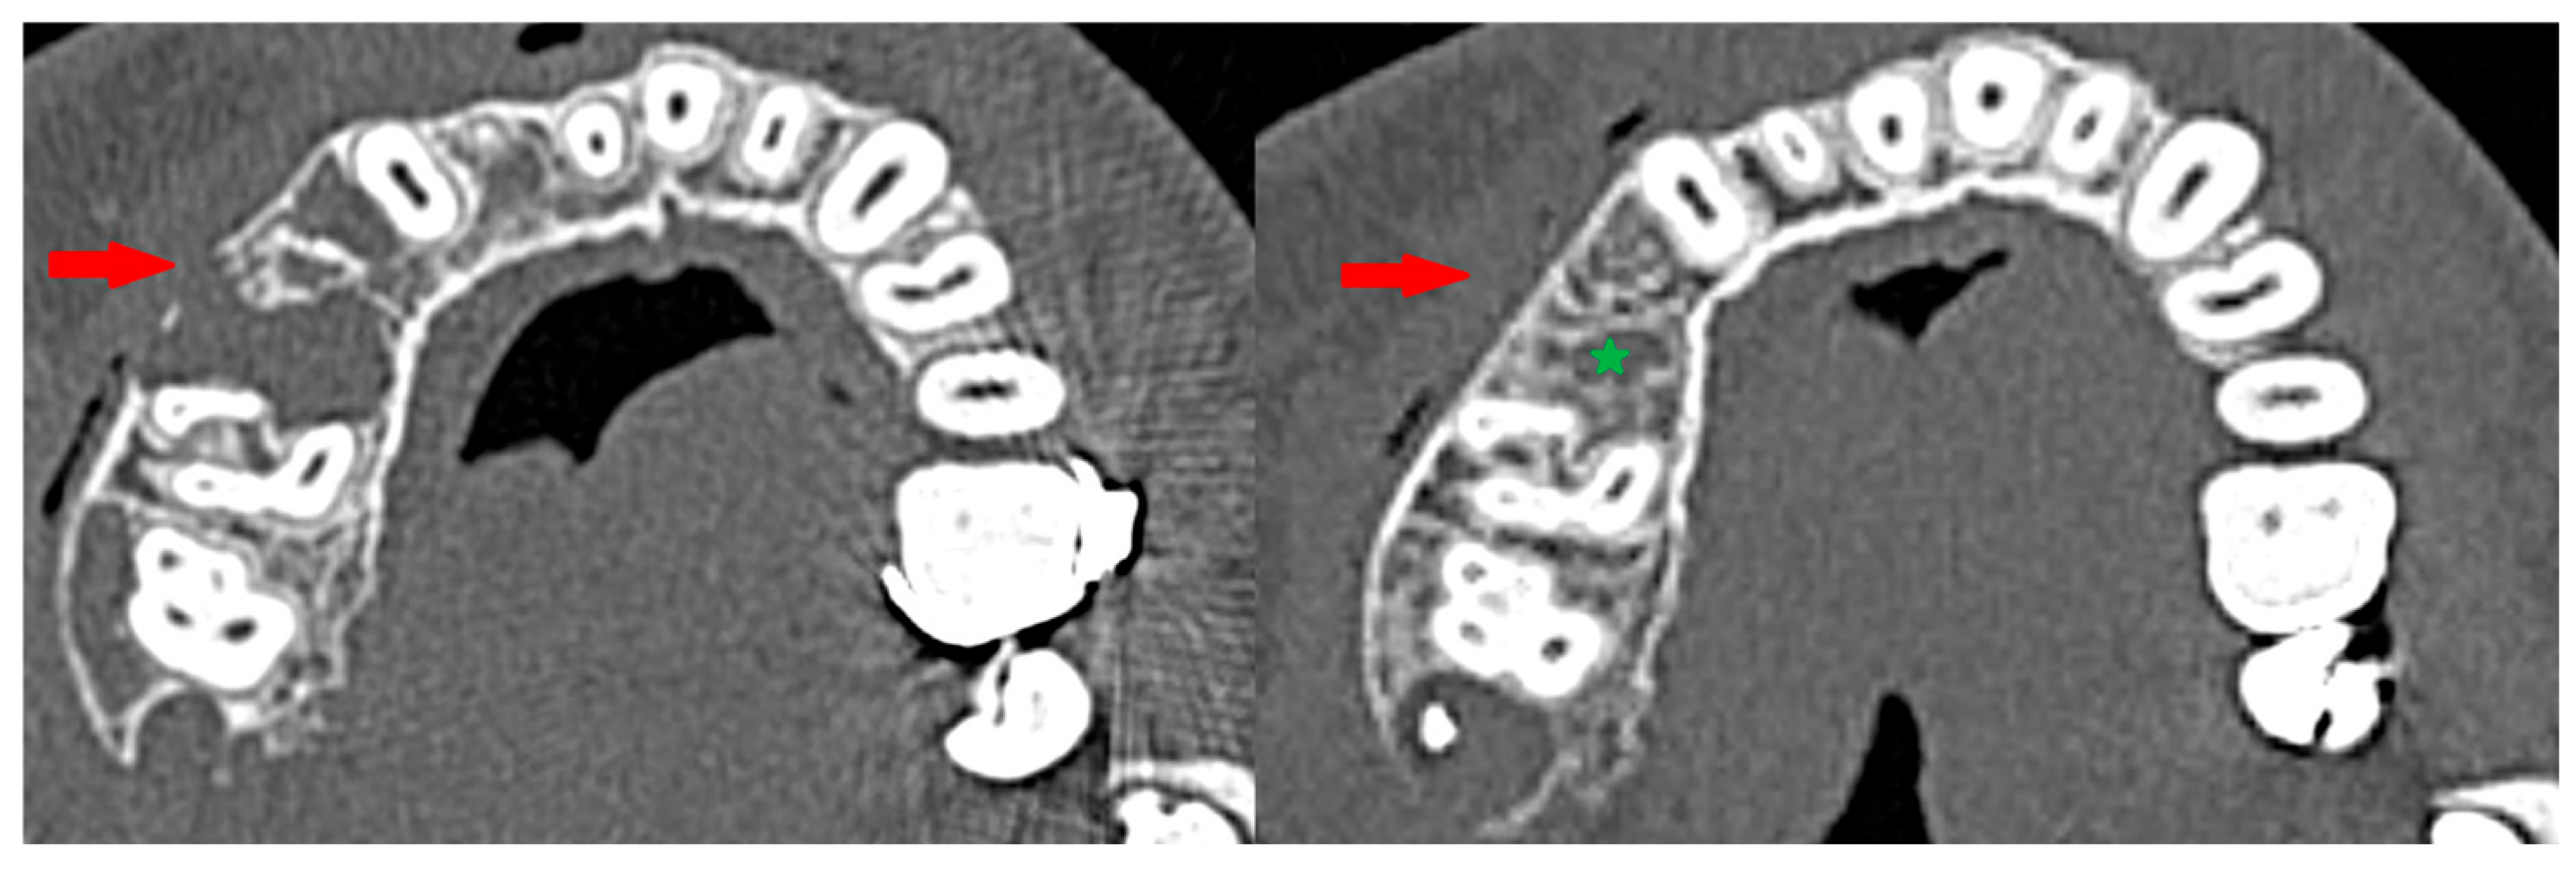

3.3. Osteosclerotic Rim (Peripheral Corticalization)